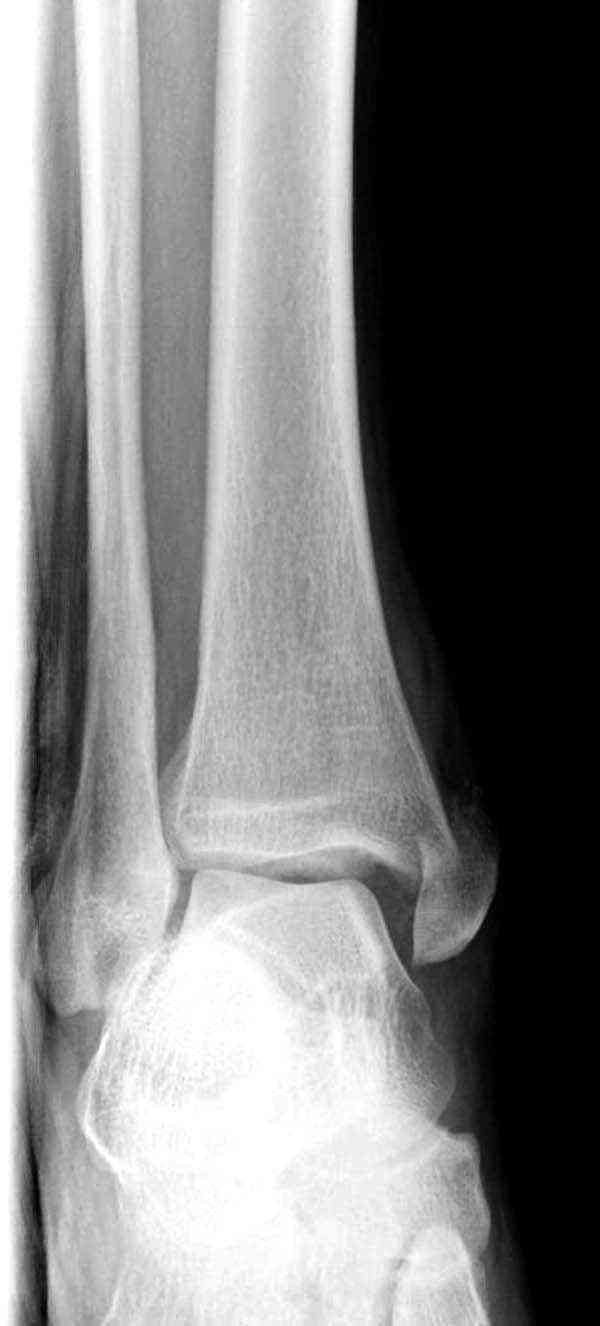

Нет первичных снимков, перелом очень низкий и под большим сомнением диагноз разрыва синдесмоза. Медиальная сторона отрепонирована на "хорошо" и, по-видимому, прорезание проволоки произошло во время операции. Без снимков трудно судить о высоте малоберцовой, а лодыжка находится в варусе. Лагирование получилось, но возле тонких шурупов передне-задний шуруп выглядит немного тяжеловато.

Здесь несколько частных случаев: перелом голеностопа со сравнительными снимками и разрыв синдесмоза, а также медиальная Hook пластина.